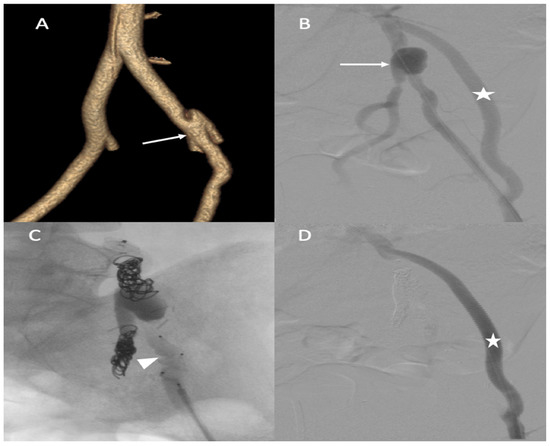

During the iliofemoral bypass, a 6 Fr introducer was inserted into the left femoral artery. The left internal iliac artery was catheterized using both a 4 F cobra catheter (COOK-MEDICAL) and a Progreat 2.7 F catheter (Terumo-Tokyo, Japan). The internal iliac artery trunk was occluded using 6 × 60 POD coils (Penumbra-Alameda, CA, USA). Then, the common internal iliac artery was occluded using second-generation 10 mm Amplatzer vascular plugs and several coils (ABBOTT). The external iliac artery was occluded by several Amplatzer Plugs (ABBOTT). One week after the intervention, he complained of acute epigastric pain and presented with hemorrhagic shock. An enhanced abdominal and pelvic CT scan showed hemoperitoneum with aneurismal rupture of the left hepatic artery and an aneurysm of the celiac trunk and common hepatic artery (Figure 5). The patient was referred in extreme emergency to the interventional radiologist. A 6 F femoral access was performed to access the celiac trunk using the 6 F RDC catheter (Cordis-Santa Clara, CA, USA). Then, the left hepatic artery aneurysm was catheterized using a Progreat 2.7 F microcatheter (Terumo-Tokyo, Japan). The rupture of the left hepatic artery was confirmed on digital subtraction angiography (DSA), and the vessel was occluded using cyanoacrylate glue and multiple coils. DSA of the celiac trunk revealed an aneurismal evolution of the celiac trunk and the common hepatic artery with an occlusion of the common hepatic artery before the gastroduodenal artery. The common hepatic artery and celiac trunk were occluded using ethylene vinyl alcohol copolymer (Onyx, ev3, USA), several interlocking coils, and IDS (Boston Scientific, Marlborough, MA, USA) (Figure 5) without any complications during the procedure.

Figure 5.

(A,B) Axial and coronal abdominal CT images pertaining to the arterial phase show the aneurysm in the left hepatic artery (arrows) with perihepatic hematoma; (C) one coil was inserted in the aneurysm (star), and then glue and multiple coils were introduced into the common hepatic artery (arrowhead).